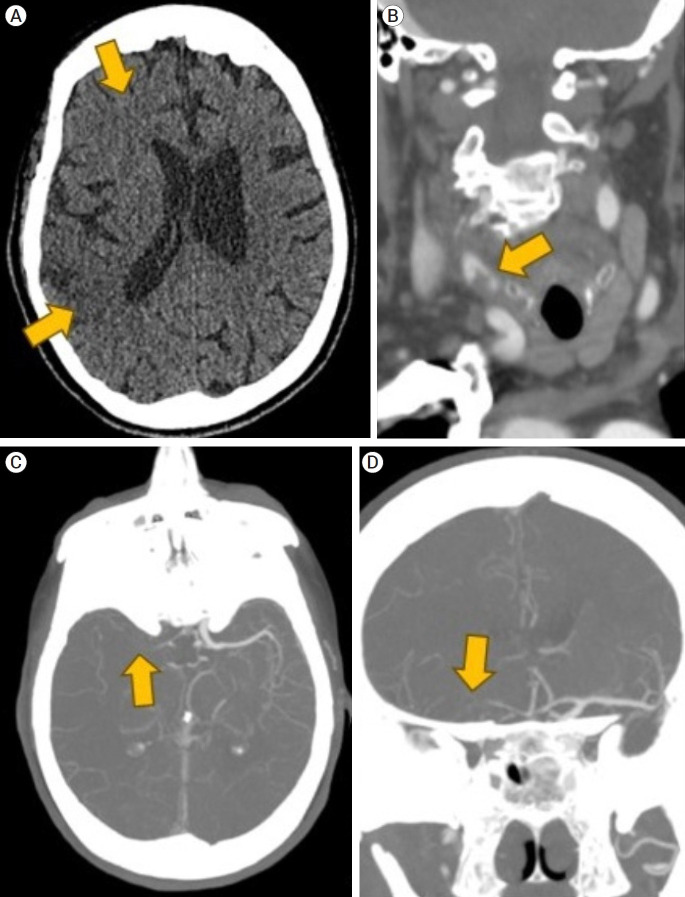

血管内治疗是目前治疗大血管闭塞引起的急性缺血性卒中的金标准治疗方法。尽管如此,严重的血管扭曲和颈动脉环的存在会阻碍手术的成功。我们报告一例83岁女性急性缺血性中风和极端扭曲,包括颈总动脉和颈内动脉连续环路,以及颈总动脉分叉串联血栓与M1段闭塞。随后,我们回顾了复杂取栓病例的技术管理方面的相关文献。血管内手术包括使用多种血管内工具通过极端的血管弯曲进行导航,使用输送装置促进手术的再灌注。手术过程中出现血管痉挛和颈内动脉袢拉直等问题。然而,成功的取栓使用适当的手术技术进行了讨论。

Endovascular therapy is the current gold standard treatment for the management of acute ischemic stroke from large vessel occlusion. Despite this, the presence of severe vascular tortuosity and cervical carotid loops can hinder the success of the procedure. We present a case of an 83-year-old female presenting with acute ischemic stroke and extreme tortuosity including common carotid artery and internal carotid artery consecutive loops, as well as a tandem common carotid artery bifurcation thrombus with an M1 segment occlusion. Subsequently, relevant literature is reviewed regarding the technical management of complex thrombectomy cases. The endovascular procedure involved navigating through extreme vascular tortuosity using multiple endovascular tools for optimal reperfusion using delivery devices to facilitate the procedure. Challenges such as vasospasm and straightening of an internal carotid artery loop occurred during the procedure. However, successful thrombectomy was performed using adequate procedural techniques discussed.